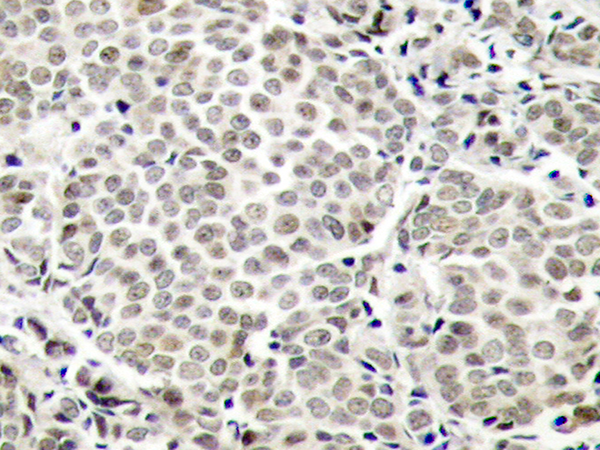

WB, IHC, IF

IHC positive control:

Human breast carcinoma

IHC Recommend dilution:

50-100